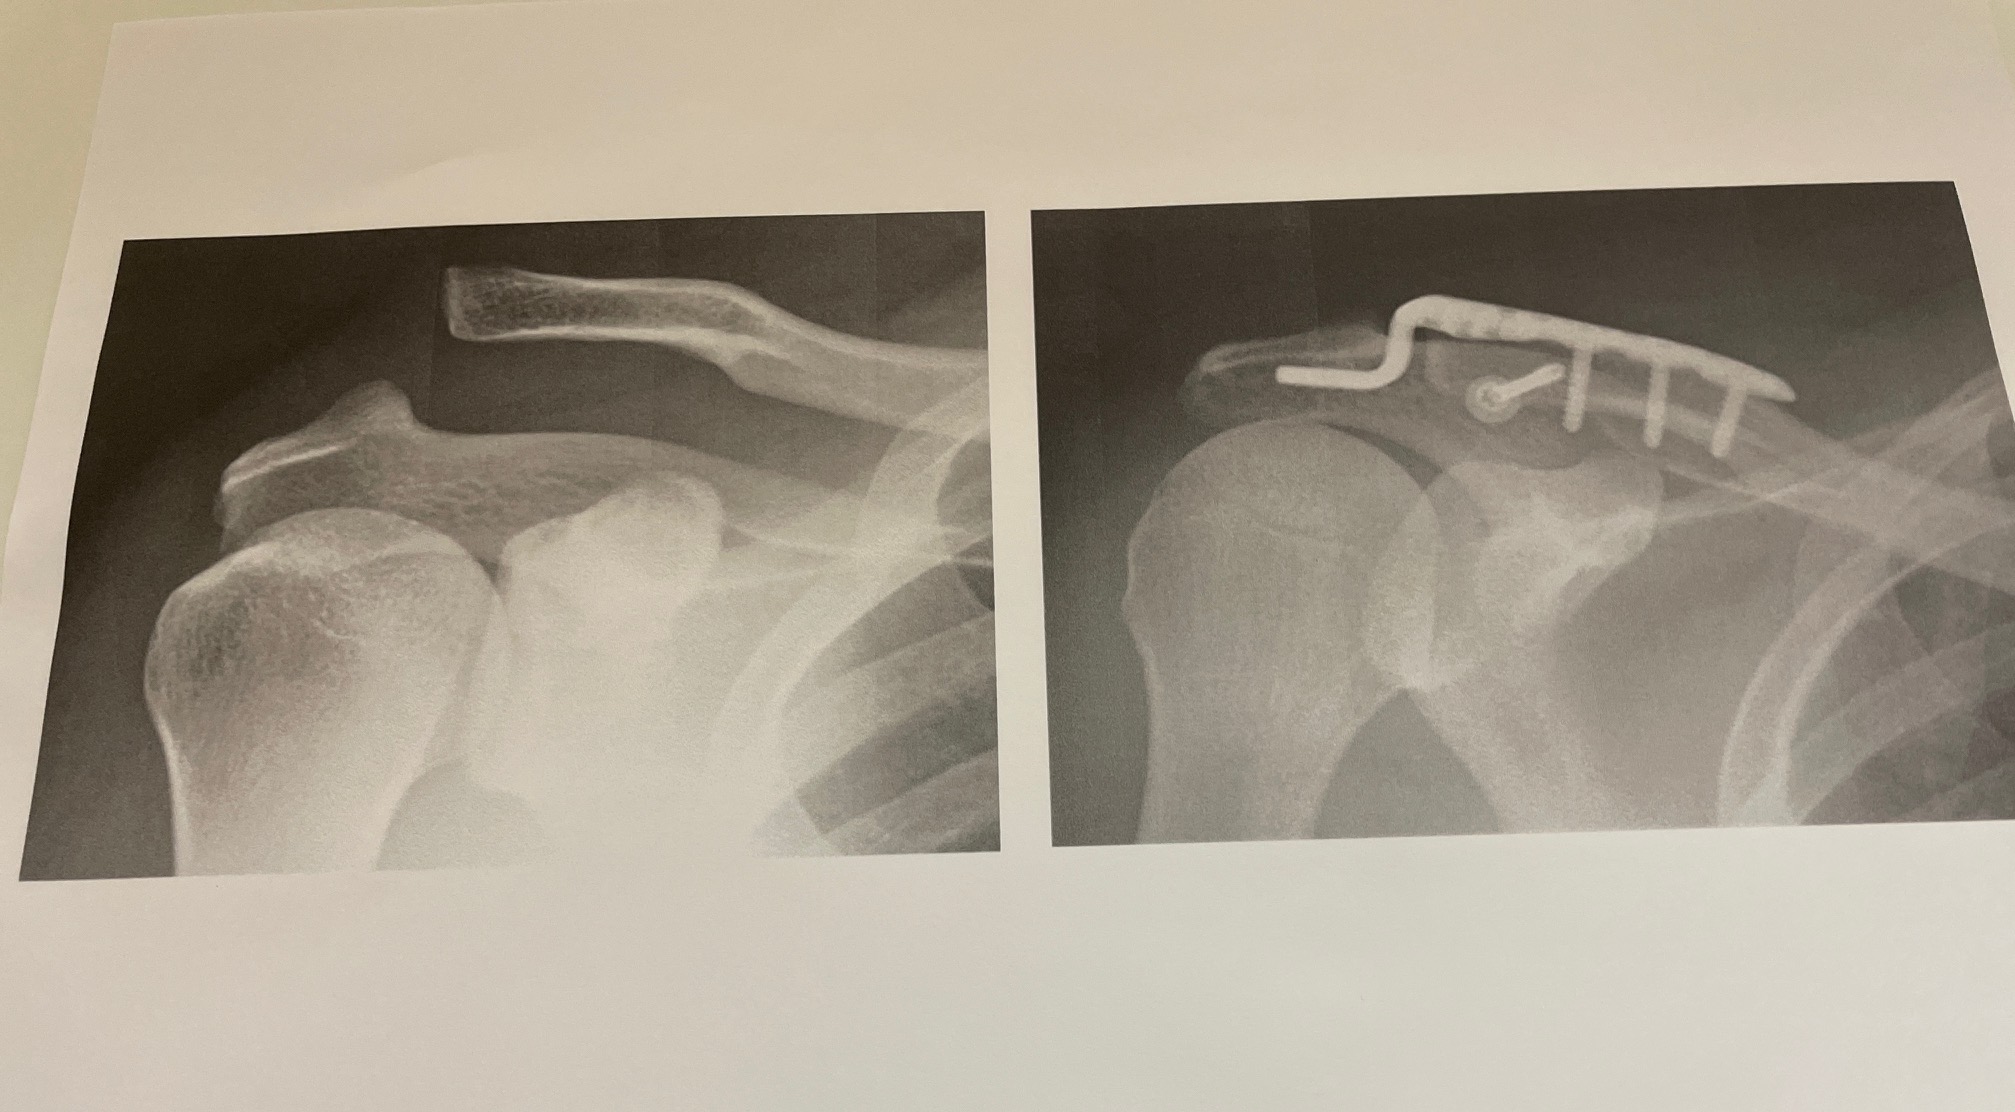

肩鎖関節 (AC) は、肩峰突起と呼ばれる肩甲骨の一部と鎖骨の間にあります。

AC 関節手術は、重度の AC 関節損傷の治療に使用されます。現時点では、ゴールドスタンダードの手術についてのコンセンサスはなく、どの手術が最適かは傷害の種類と重症度によって異なります。

AC 関節損傷は、その重症度に応じてグレード 1 からグレード 5 に分類され、グレードの高い損傷ほど重度になります。

グレード 3 の損傷を外科的に修復する必要があるかどうかについては、研究が分かれています。グレード 3 の AC 関節損傷は、付着している靭帯が完全に破壊され、肩甲骨と鎖骨が完全に分離します。

AC関節手術は、肩甲骨と鎖骨の間のAC関節の損傷を治療します。通常、手術が必要になるのは重傷の場合のみです。

手術には多くの種類があり、どの種類が最適であるかは、怪我の種類や重症度などの要因によって異なります。手術後にスポーツに復帰できる人はたくさんいます。